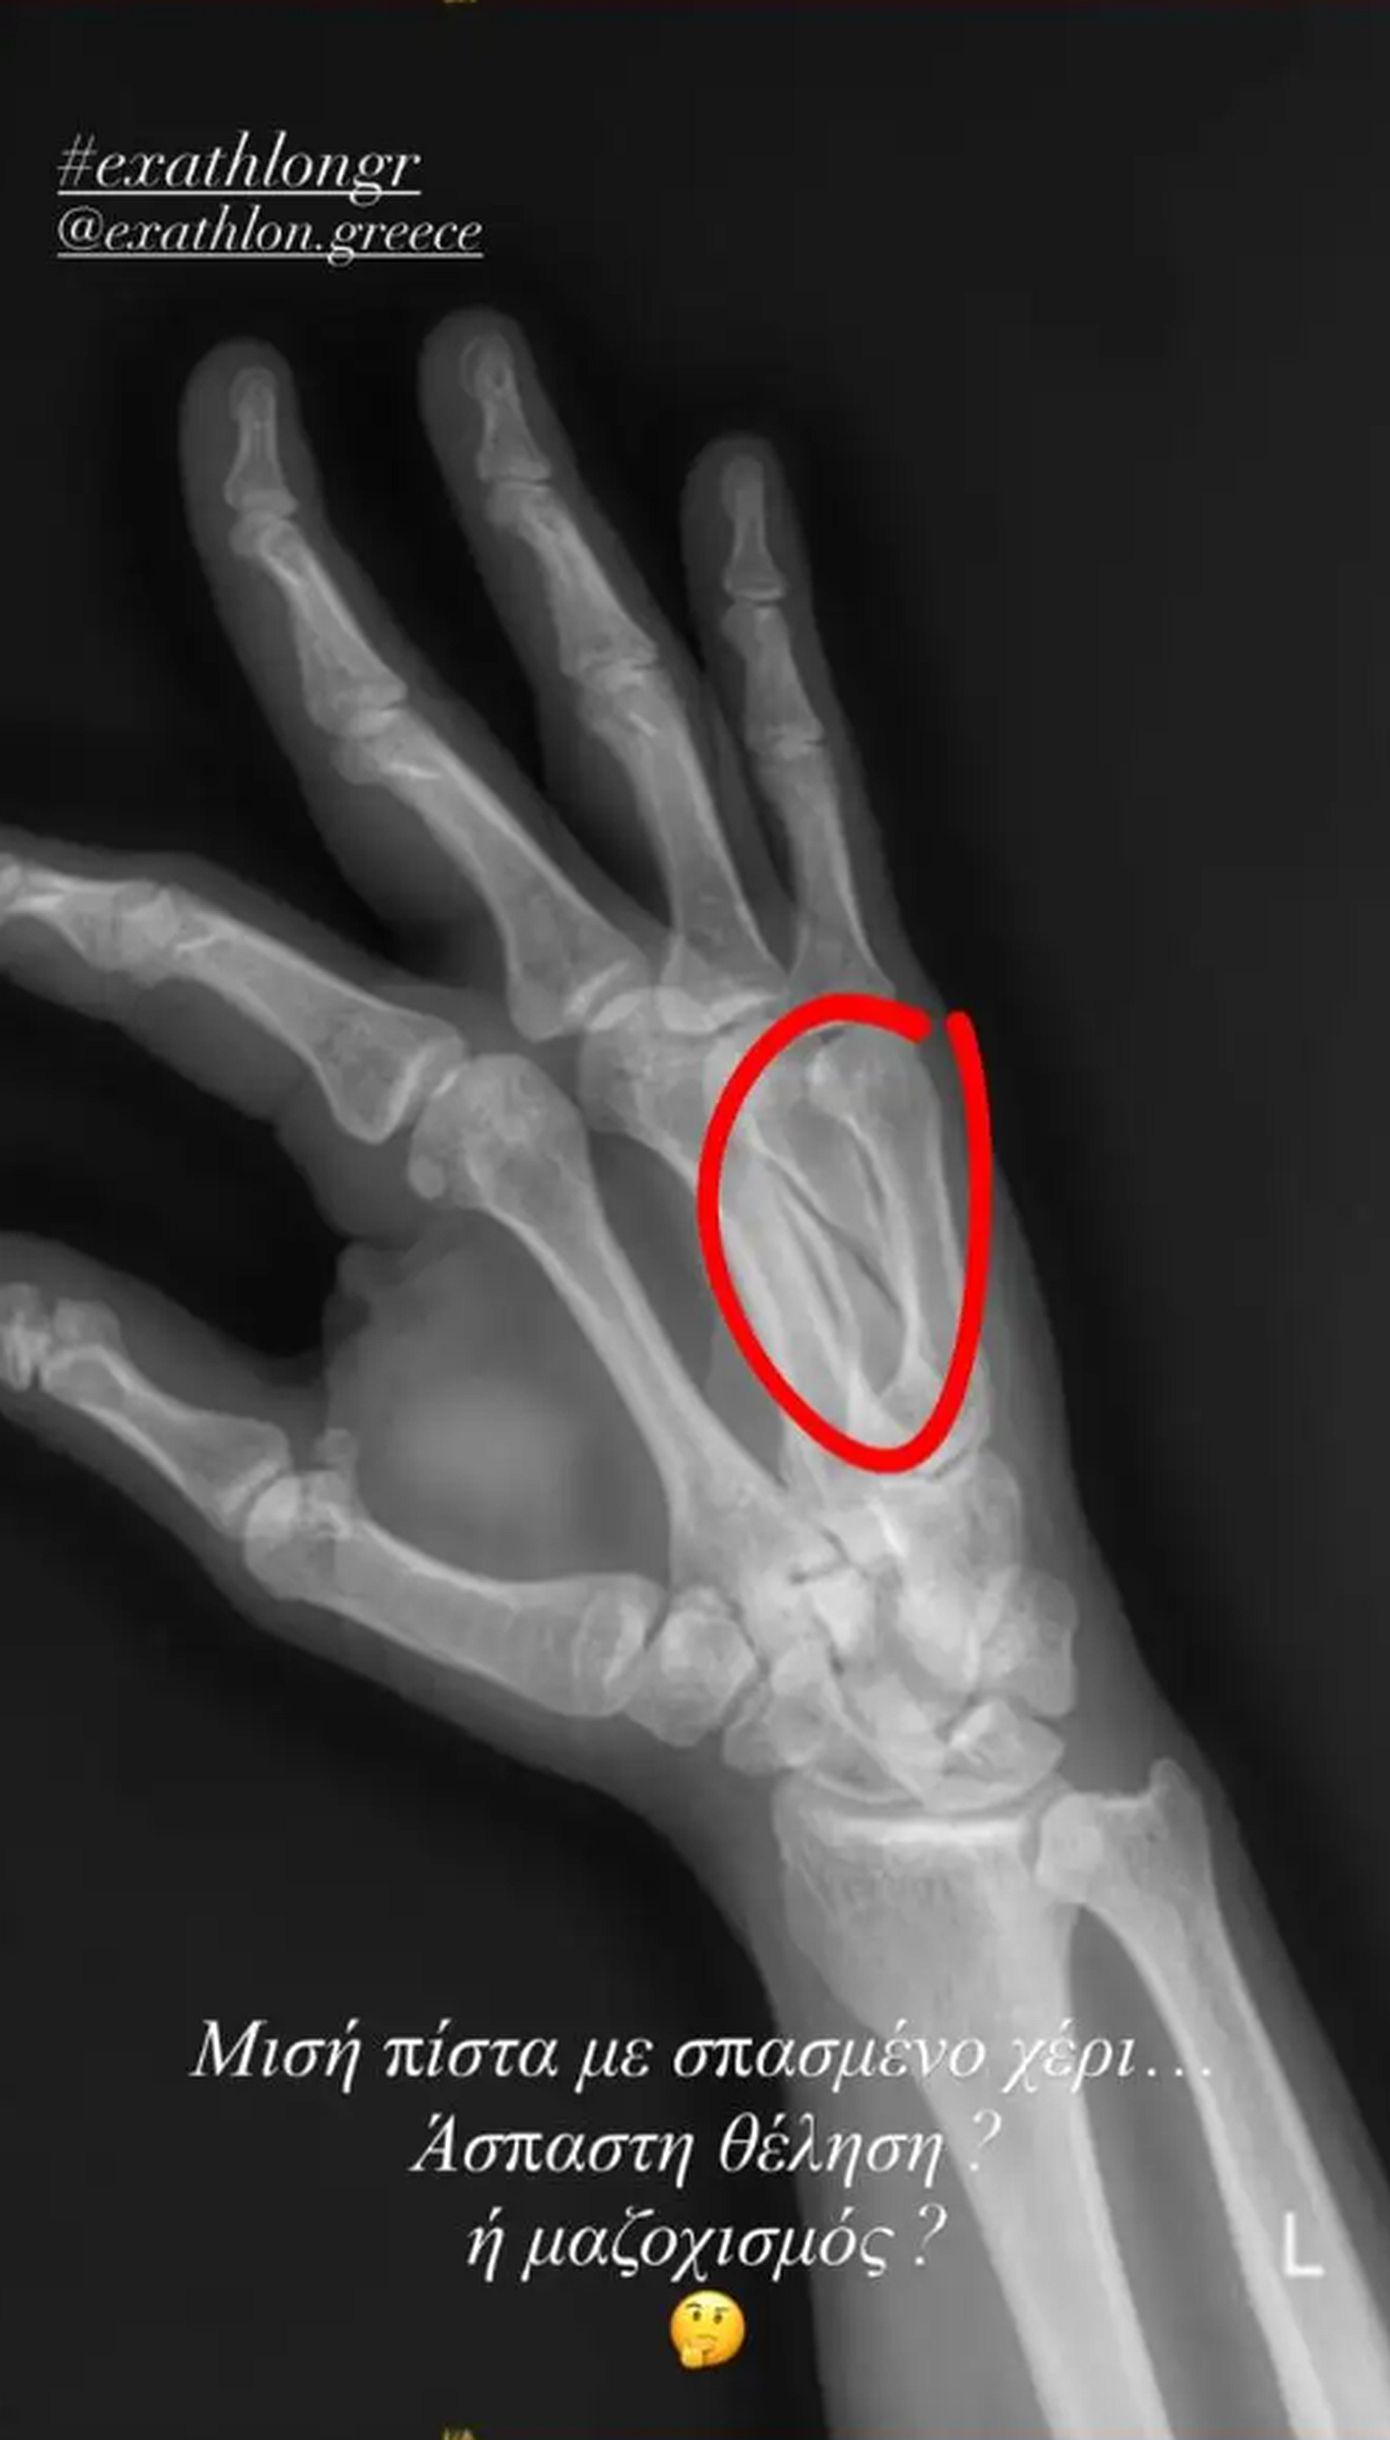

Παράλληλα, δε, ο Στάθης Σχίζας επέλεξε να μοιραστεί με τους διαδικτυακούς του φίλους και μια εικόνα από την ακτινογραφία που αποτυπώνει το σπάσιμο του χεριού του. «Μισή πίστα με σπασμένο χέρι… Άσπαστη θέληση ή μαζοχισμός;» αναρωτιέται χαρακτηριστικά ο πρώην παίκτης του Exathlon στον προσωπικό του λογαριασμό στο Instagram.